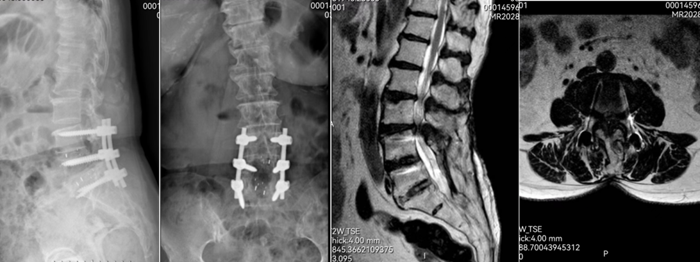

患者胡某术前影像

UBE椎管减压术后影像显示椎管双侧减压充分、关节突保护良好